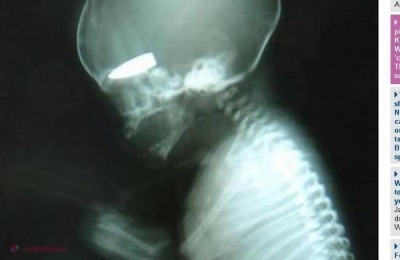

Copiii nenăscuţi ai femeilor din Siria au devenit în ultima perioadă ţintele unui joc de război şocant. Lunetişti din zonele de conflict ucid fetuşii chiar în uterele mamelor şi sunt premiaţi cu ţigări dacă reuşesc să îşi atingă ţinta, povesteşte un chirurg britanic, întors recent dintr-o misiune de voluntariat într-un spital sirian, pentru Daily Mail, citat de „Gândul”.

Chirurgul David Nott descrie situaţia în care sunt puşi civilii prinşi între trupele guvernului şi rebeli ca fiind „un iad mai rău decât iadul" şi spune că în cei 20 de ani în care a lucrat ca voluntar în zone de război nu a mai văzut alte situaţii în care ţintele să fie femei însărcinate.

„Femeile erau împuşcate prin uter, aşa că aceasta era probabil ţinta lor. Nici nu pot să încep să explic măcar cât de groaznic a fost", spune medicul britanic.

„De la primii pacienţi care ajungeau de dimineaţă puteai să îţi dai seama ce urma să vezi tot restul zilei. Era un joc", adaugă el.

„Într-o zi erau împuşcaţi în zona inghinală. În ziua următoare erau doar răni în partea stângă a pieptului. După aceea, nu vedeam nicio rană în zona pieptului, toate erau în zona gâtului", povesteşte Nott care spune că pe plan local se credea că lunetiştii ar fi lucrat pentru regimul lui Bashar al-Assad.